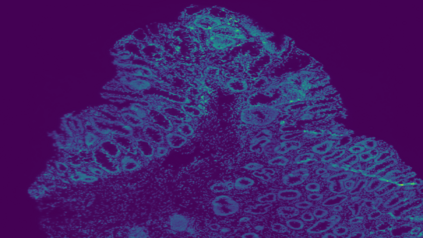

The usage of chemical imaging technologies is becoming a routine accompaniment to traditional methods in pathology. Significant technological advances have developed these next generation techniques to provide rich, spatially resolved, multidimensional chemical images. The rise of digital pathology has significantly enhanced the synergy of these imaging modalities with optical microscopy and immunohistochemistry, enhancing our understanding of the biological mechanisms and progression of diseases. Techniques such as imaging mass cytometry provide labelled multidimensional (multiplex) images of specific components used in conjunction with digital pathology techniques. These powerful techniques generate a wealth of high dimensional data that create significant challenges in data analysis. Unsupervised methods such as clustering are an attractive way to analyse these data, however, they require the selection of parameters such as the number of clusters. Here we propose a methodology to estimate the number of clusters in an automatic data-driven manner using a deep sparse autoencoder to embed the data into a lower dimensional space. We compute the density of regions in the embedded space, the majority of which are empty, enabling the high density regions to be detected as outliers and provide an estimate for the number of clusters. This framework provides a fully unsupervised and data-driven method to analyse multidimensional data. In this work we demonstrate our method using 45 multiplex imaging mass cytometry datasets. Moreover, our model is trained using only one of the datasets and the learned embedding is applied to the remaining 44 images providing an efficient process for data analysis. Finally, we demonstrate the high computational efficiency of our method which is two orders of magnitude faster than estimating via computing the sum squared distances as a function of cluster number.